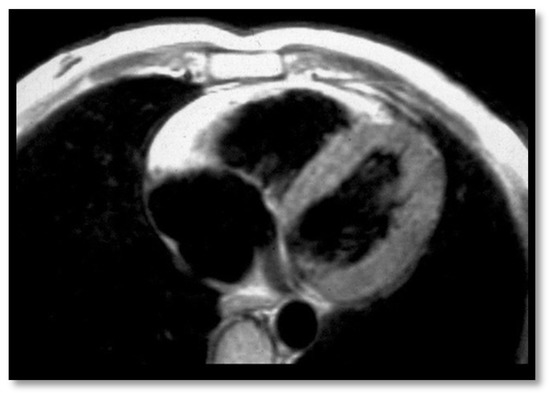

- Delayed enhancementThe significance of delayed enhancement in cardiac MRI is fibrosis, edema, or inflammation [49]. It is not possible to clearly differentiate the exact cause of the increase in the extracellular volume. The abnormal tissue causes gadolinium retention while normal myocardial tissue does not. It is estimated that approximately 67% of patients with ARVC have delayed enhancement of the ventricular walls. In the study of Tandri et al. [49], 6 out of 10 patients with ARVC presented induced VT during electrophysiological study, and 4 did not have induced VT. It is relevant to mention that among patients with inducible VT, all six had delayed enhancement in cardiac MRI, and among those who were not inducible, only one had delayed enhancement in MRI.